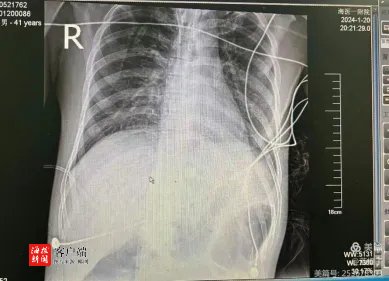

1月18日,41岁的退役军人丰大哥突发胸闷、气促,血氧低至75%,由肝胆外科转入海南医学院第一附属医院重症医学科。丰大哥转入重症医学科后,为了进一步明确诊断,管床医师、规培医师及护理老师冒着在路上抢救的风险紧急将丰大哥送往CT室进行胸部CTA检查。CT结果显示丰大哥未见肺栓塞征象,但两肺大片炎性渗出,80%~90%的肺功能已经丧失,也就是俗称的“大白肺”。

1月22日,丰大哥的呼吸功能得到明显改善,呼吸机参数及ECMO参数下调,再一次复查胸部CT后,发现丰大哥一夜间变白的双肺逐渐恢复了清晰,行撤机试验评估已达撤机标准,予当天撤除ECMO。1月26日丰大哥成功转出ICU。